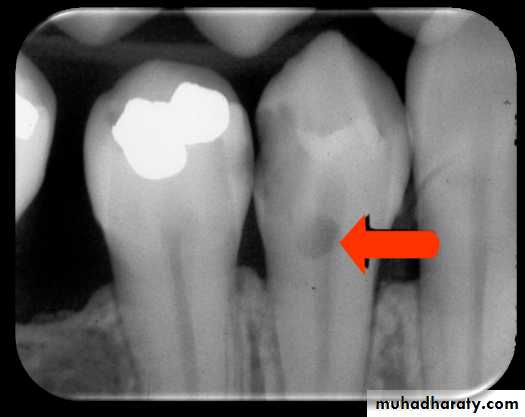

Proximal caries

Caries found between two teeth is termed interproximal caries. On a dental image, interproximal caries is typically seen at or just below (apical to) the contact point. This area is difficult, if not impossible, to examine clinically with an explorer. As the caries progresses inward through the enamel of the tooth, it assumes a triangular configuration; the apex (or point) of the triangle is seen at the dentino-enamel junction (DEJ).

As the caries reaches the DEJ, it spreads laterally and continues into dentin. Another triangular configuration is seen in dentin; this time the base of the triangle is along the DEJ, and the apex is pointed toward the pulp chamber

Proximal caries classified according to its severity

Incipient inter proximal caries extends less than half way through the thickness of enamelModerate inter proximal caries extends more than half way through enamel

Advanced inter proximal caries extends to or through the dentanoenamel junction and into dentin but does not extend through the dentin more than half the distance toward the pulp (affects both enamel and dentin(Severe inter proximal caries extends through enamel and through dentin more than half distance toward the pulp (involve both enamel and dentin(